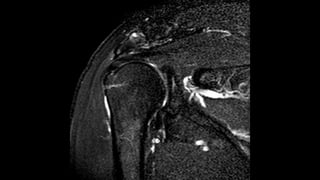

O documento aborda lesões no ombro, dividindo-as por faixas etárias: fraturas de clavícula em crianças, luxações em adultos e fraturas do úmero proximal em idosos. Descreve também técnicas de avaliação radiográfica e suas variações, incluindo incidências específicas para diagnóstico. Além disso, são mencionados métodos de imagem alternativos para a avaliação de partes moles e condições articulares.